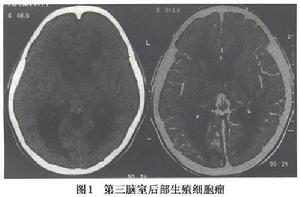

平掃CT可見與腦灰質等密度或稍高密度,松果體區生殖細胞瘤鈣化的幾率較鞍區生殖細胞瘤高得多當松果體區生殖細胞瘤生長過程中有時將鈣化的松果體(呈彈丸狀)包繞在其中故鈣化的“彈丸”可能在瘤內,也可在腫瘤的周邊常在側方或後方偶可被推擠至前方。腫瘤外形呈圓形不規則型或呈蝴蝶形,後者在診斷生殖細胞瘤有著特徵性價值正常人松果體鈣化率約為40%,而有生殖細胞瘤患者的松果體鈣化率近100%;鞍上生殖細胞瘤可無鈣化或細小的鈣化(圖1)。

胚生殖細胞瘤增強CT:當CT平掃發現病變的情況下應立即注藥做CT強化掃描表現為中度到明顯的均勻一致的強化少數強化不均勻,可顯示較小的囊變。故兒童或青少年,CT發現有松果體區稍高密度腫物,注藥有均勻強化(少數可不均勻),若有彈丸狀鈣化則強烈提示為生殖細胞瘤鞍上生殖細胞瘤位於中線漏斗和(或)垂體進入鞍內,侵犯神經垂體也不少見鞍上生殖細胞瘤可為圓形或分葉狀,CT平掃和增強與松果體區相似但有的學者指出此部位的生殖細胞瘤鮮有鈣化發生。除了上述“單發性”腫瘤之外關於“多發性”的生殖細胞瘤最典型的是在做CT檢查時同時發現2或3個生殖細胞瘤。

CT檢查對生殖細胞瘤有很大價值,尤其對腫瘤的鈣化及腦室擴大或移位情況提供重要的資料。不同亞型的生殖細胞瘤有其特有的表現有時結合臨床甚至可作出腫瘤定性診斷